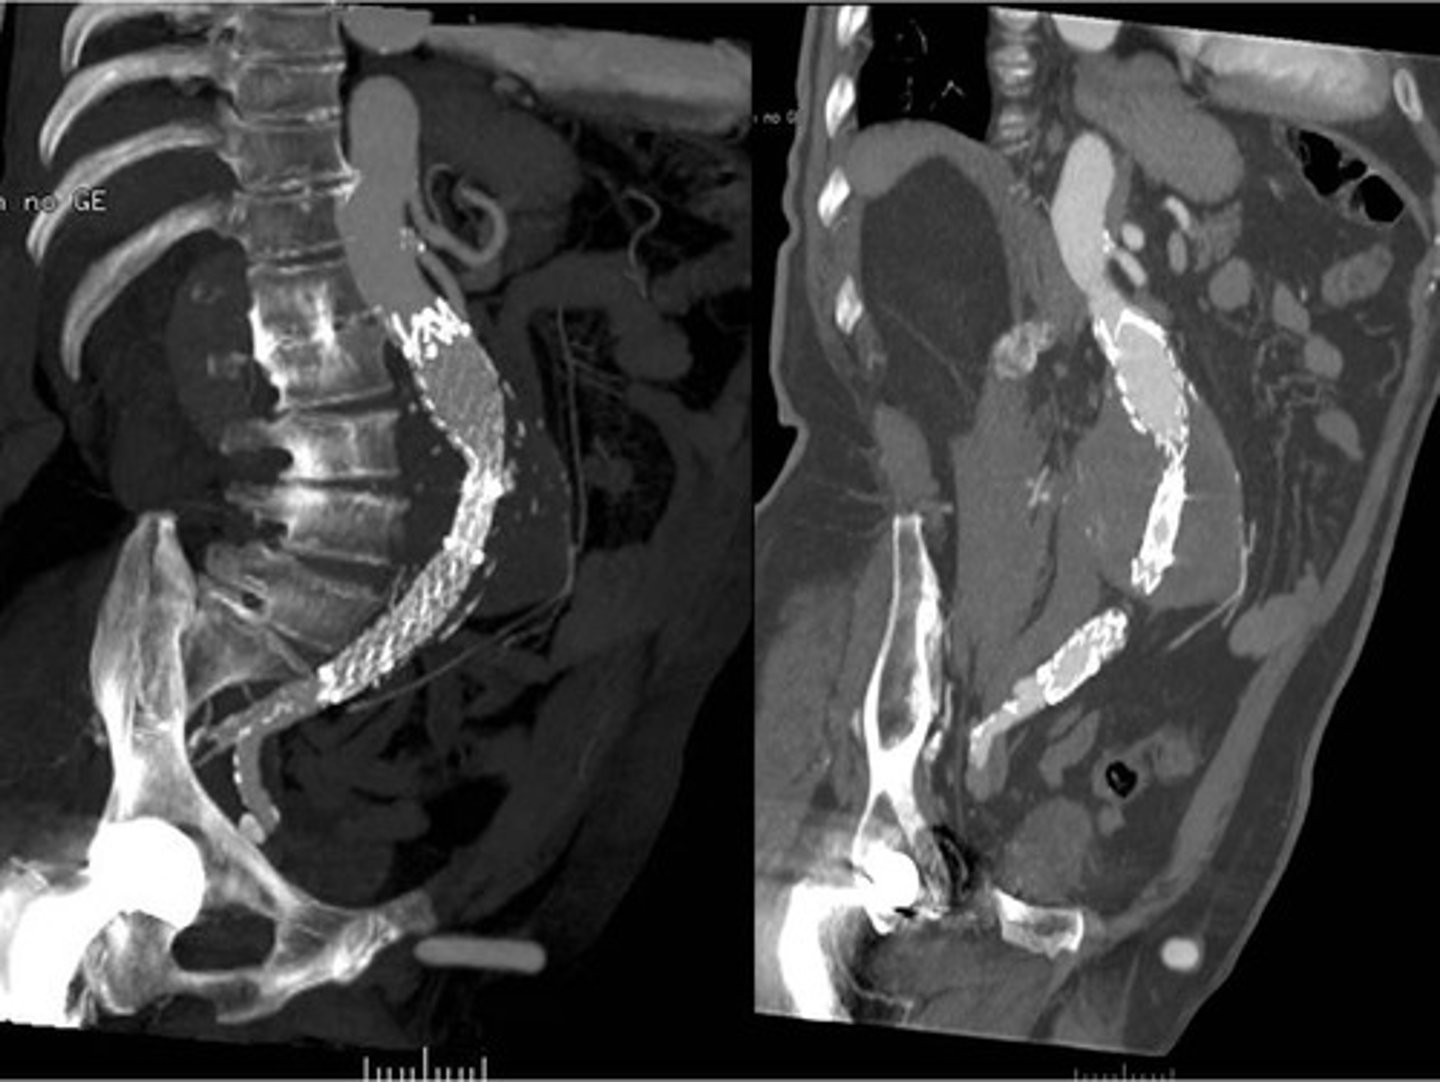

Abdominal aortic aneurysm on CT

Stent due to AAA